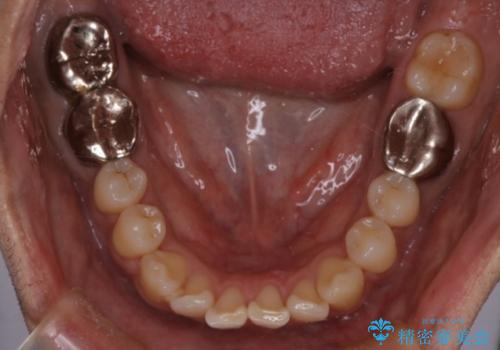

- 前歯の出ているのが気になる、下唇を噛んで痛いとのことで来院された患者様です。マウスピース矯正をご希望でした。

奥歯の噛み合わせはしっかりしていましたので、奥歯の動きは最小限にし、前歯の並びに集中した治療計画+インビザラインのシミュレーションを作成しました。

奥歯の噛み合わせは整っていたため、前歯の並びを美しく修正することに専念できました。マウスピース矯正による治療で短期間で改善しました。